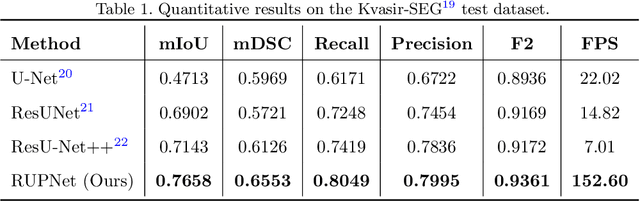

RUPNet: Residual upsampling network for real-time polyp segmentation

Colorectal cancer is among the most prevalent cause of cancer-related mortality worldwide. Detection and removal of polyps at an early stage can help reduce mortality and even help in spreading over adjacent organs. Early polyp detection could save the lives of millions of patients over the world as well as reduce the clinical burden. However, the detection polyp rate varies significantly among endoscopists. There is numerous deep learning-based method proposed, however, most of the studies improve accuracy. Here, we propose a novel architecture, Residual Upsampling Network (RUPNet) for colon polyp segmentation that can process in real-time and show high recall and precision. The proposed architecture, RUPNet, is an encoder-decoder network that consists of three encoders, three decoder blocks, and some additional upsampling blocks at the end of the network. With an image size of $512 \times 512$, the proposed method achieves an excellent real-time operation speed of 152.60 frames per second with an average dice coefficient of 0.7658, mean intersection of union of 0.6553, sensitivity of 0.8049, precision of 0.7995, and F2-score of 0.9361. The results suggest that RUPNet can give real-time feedback while retaining high accuracy indicating a good benchmark for early polyp detection.